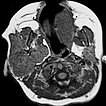

Die transversale, T1-gewichtete, native MRT des oberen Halses zeigt den subkutan gelegenen Tumor, der klar solide ist und scharf abgrenzbar zum umgebenden Gewebe. Das Mädchen ist jetzt 12 Monate alt, der Tumor hat sich nicht zurückgebildet.

Die transversale, T2-gewichtete, fettgesättigte MRT des oberen Halses zeigt den subkutan gelegenen Tumor nochmal sehr klar als hyperintense, scharf abgrenzbare Raumforderung mit zentralen Flow-voids als Zeichen der starken Perfusion. Typisches Bild eines subkutan gelegenen, infantilen Hämangioms.

Die koronare Inversion-Recovery-Sequenz (MRT) zeigt nochmals sehr gut die Ausdehnung des Hämangioms. Die Signalgebung ist isointens zum Hirngewebe. Es handelt sich klar um eine solide Raumforderung.